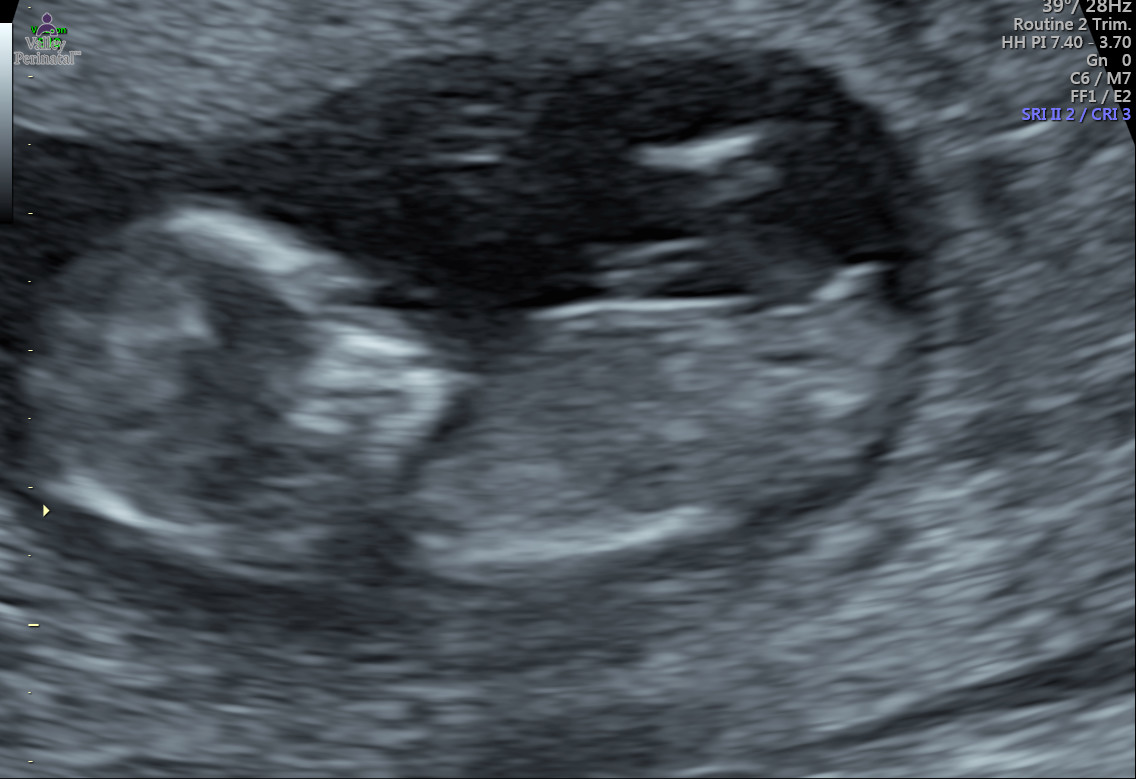

Attachment 35080

This is the same baby during the same scan. The sonographer had the perfect shot of the full nub and for whatever reason she moved the probe and gave this shot of part of the nub. The nub looked flat and it kinda curved downward. She told me that she couldn't tell me what it was because it can go either way. She mentioned that was pointing down but it was also sticking up.

There's no video and she wouldn't let me record. The nub was completely flat in the ultrasound and it came up a little and curved down like a hook a little. The tip look a little like a half circle.